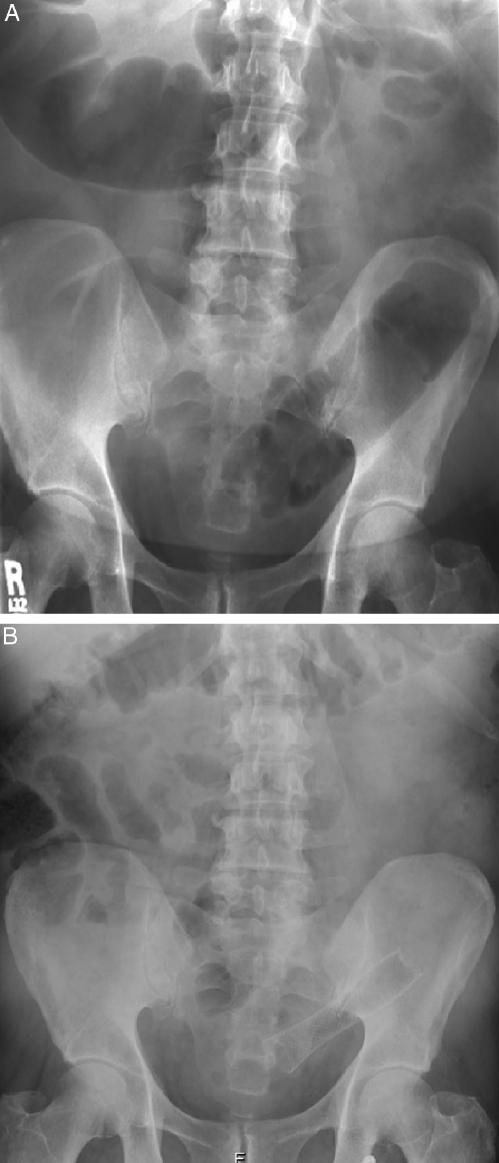

Stents were placed successfully in 17 of 21 patients (81%) with colorectal obstruction. Placement was achieved endoscopically in 13 patients and radiologically in 4. Ten self-expandable metallic stents were used as a bridge to surgery, and 7 were used for palliation. The obstructions were located in the sigmoid colon (11 patients), the rectosigmoid (3), the splenic flexure, the hepatic flexure, and the rectum. Malignant obstruction was noted in 14 patients. One patient with malignancy experienced a sigmoid perforation, and 2 patients with benign disease had complications (1 stent migration and 1 re-obstruction). Stent patency in obstruction secondary to colonic adenocarcinoma was 100% in our follow-up period (range, 5 to 15 months).